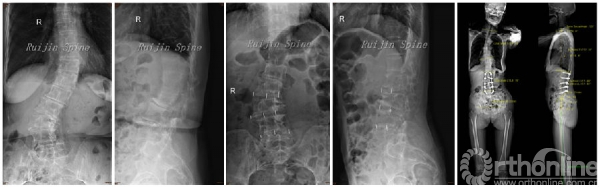

笔者所在上海瑞金医院脊柱外科团队最近几年对于应用微创手术治疗ASD进行了积极的探索,我们对于ASD患者常规进行分期手术,首先在顶椎邻近椎间隙经侧方(DLIF)或侧前方(OLIF)植入椎体间融合器,然后拍摄站立位片,重新评估固定融合范围、减压和截骨等必要性,根据患者的实际情况在1-4周以后进行后方手术(经皮椎弓根螺钉或者Wiltse入路椎弓根螺钉固定),早期随访取得了较为满意的结果。分期手术不但缩短了每次手术的麻醉时间,降低了老年患者的麻醉和手术风险,更有机会让我们重新评估畸形的矫正策略。我们的结果也发现,经过一期手术以后,的确可以缩短固定融合的范围。(图1)

图1 71岁女性,严重腰椎侧弯,按照术前的X片,需要进行长节段的固定融合,并进行截骨矫形。我们先经侧方植入椎体将融合器,术后X片提示畸形已明显矫正,我们只需要进行短节段的固定融合,无需进行截骨矫形,即可获得很好的矫形效果